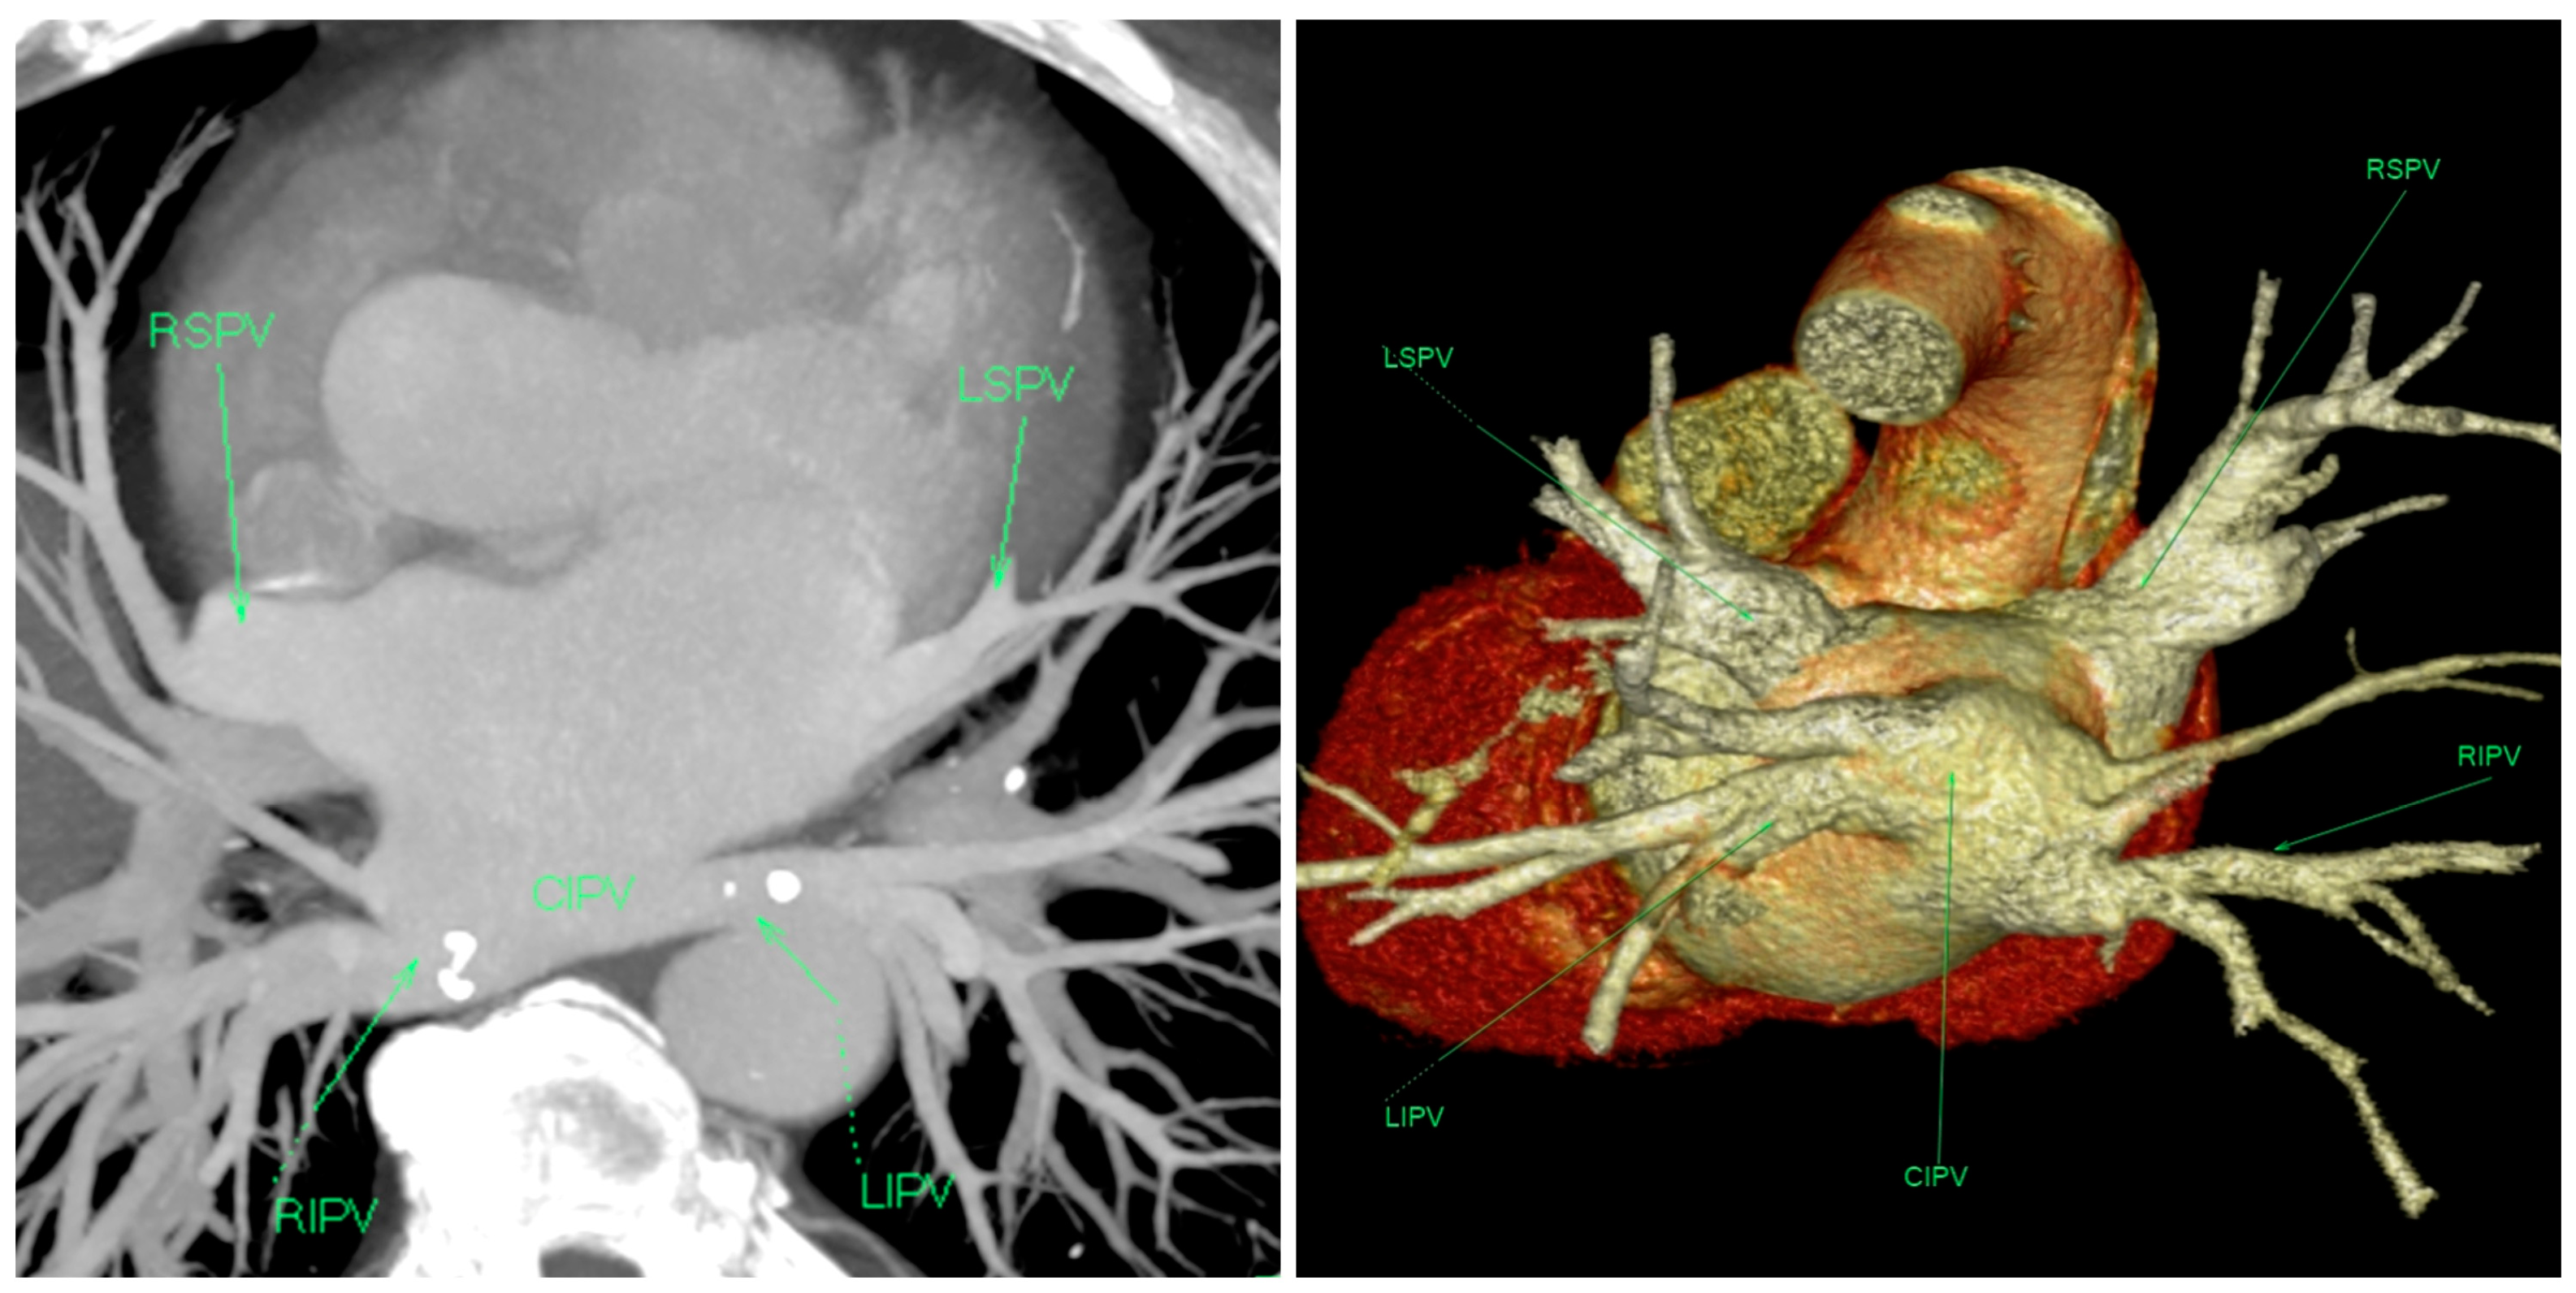

2. Case Presentation